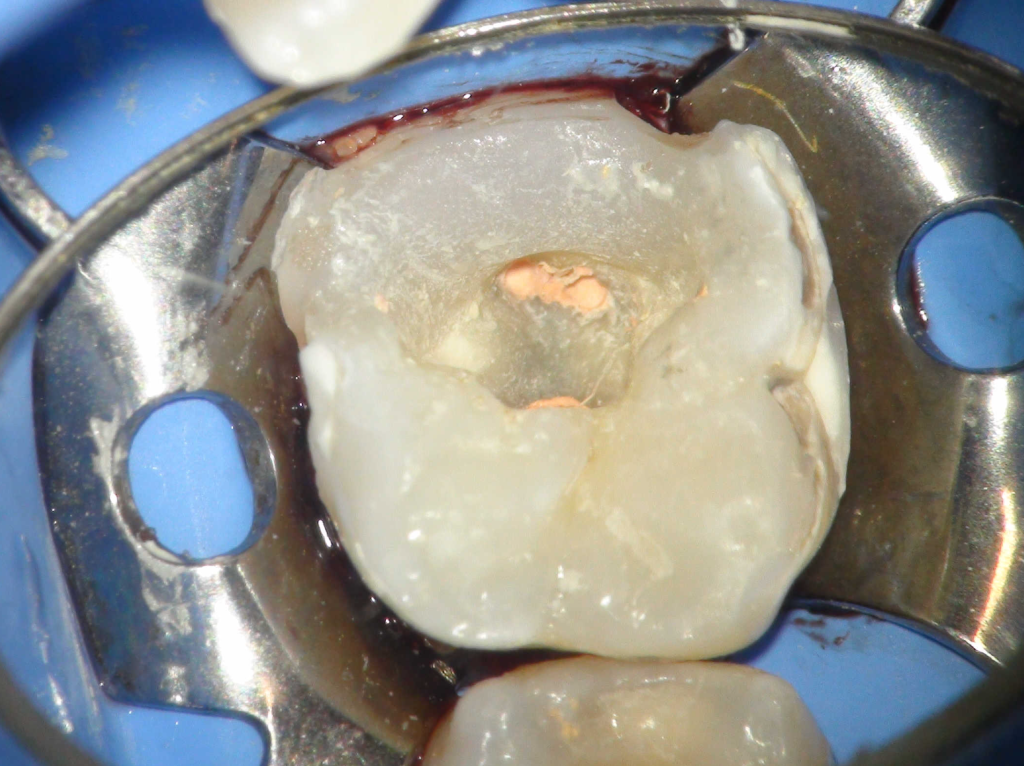

Pulpotomía biodentine + reco preendio